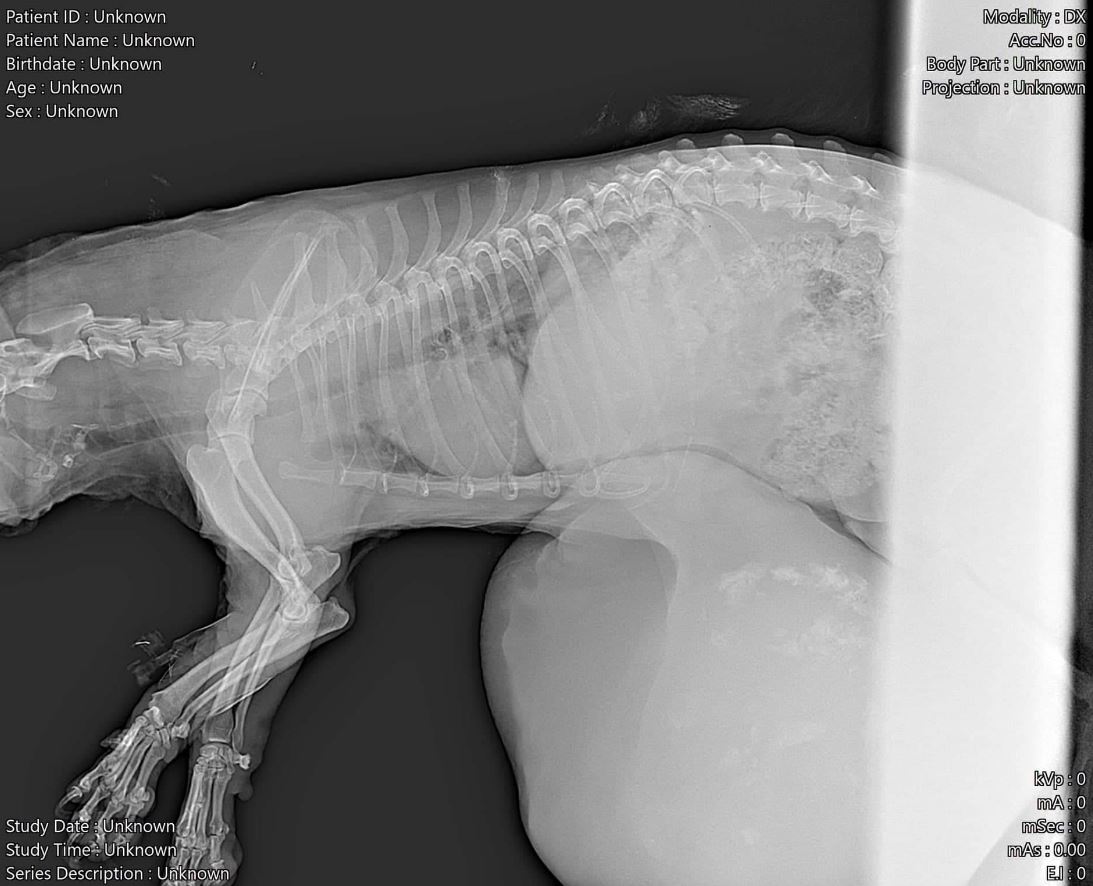

Mal angenommen ein Mensch wiegt 70 Kg. Der arme Mensch hat einen Tumor. Aber sich vorzustellen, dass der Tumor 40 Kg wiegt ist unvorstellbar, oder?! Es ist wirklich unvorstellbar, wie lange das kleine, alte Hundemädchen Elfe gelitten hat, zur Bewegungsunfähigkeit verdammt weil ihr Tumor 2,5 Kg wog, bei einem Eigengewicht von 4,5 Kg. Es ist unvorstellbar wie lange sich das Menschen angeschaut haben müssen, ihren Hund einfach da liegen ließen und nichts machten. Doch, eines Tages machten sie was. Sie brachten Elfchen zum Tierarzt zum einschläfern. Iwo der Tierschützer aus Ruse, der sich so aufopfernd um die Hunde in dem schrecklichen Kettentierheim kümmert, war zufällig auch beim Tierarzt. Er nahm sich dem Elfchen an, denn es war ihm unerträglich, der Kleinen nicht wenigstens die Chance zu geben, leben zu dürfen. Ein neues Leben ohne diesen riesigen Tumor.

Und so wurde das Elfchen operiert. Schaut euch das Größenverhältnis der Hände des Tierarztes und des Tumors an…. Zum Glück war das riesen Ding klar abgegrenzt und nur nach außen gewachsen, so dass er sich gut entfernen ließ. Das kleine alte Mädel hat trotz der jahrelangen Vernachlässigung nicht aufgegeben und ist unglaublich tapfer. Sie kämpft weil sie spürt ihr Martyrium hat ein Ende.